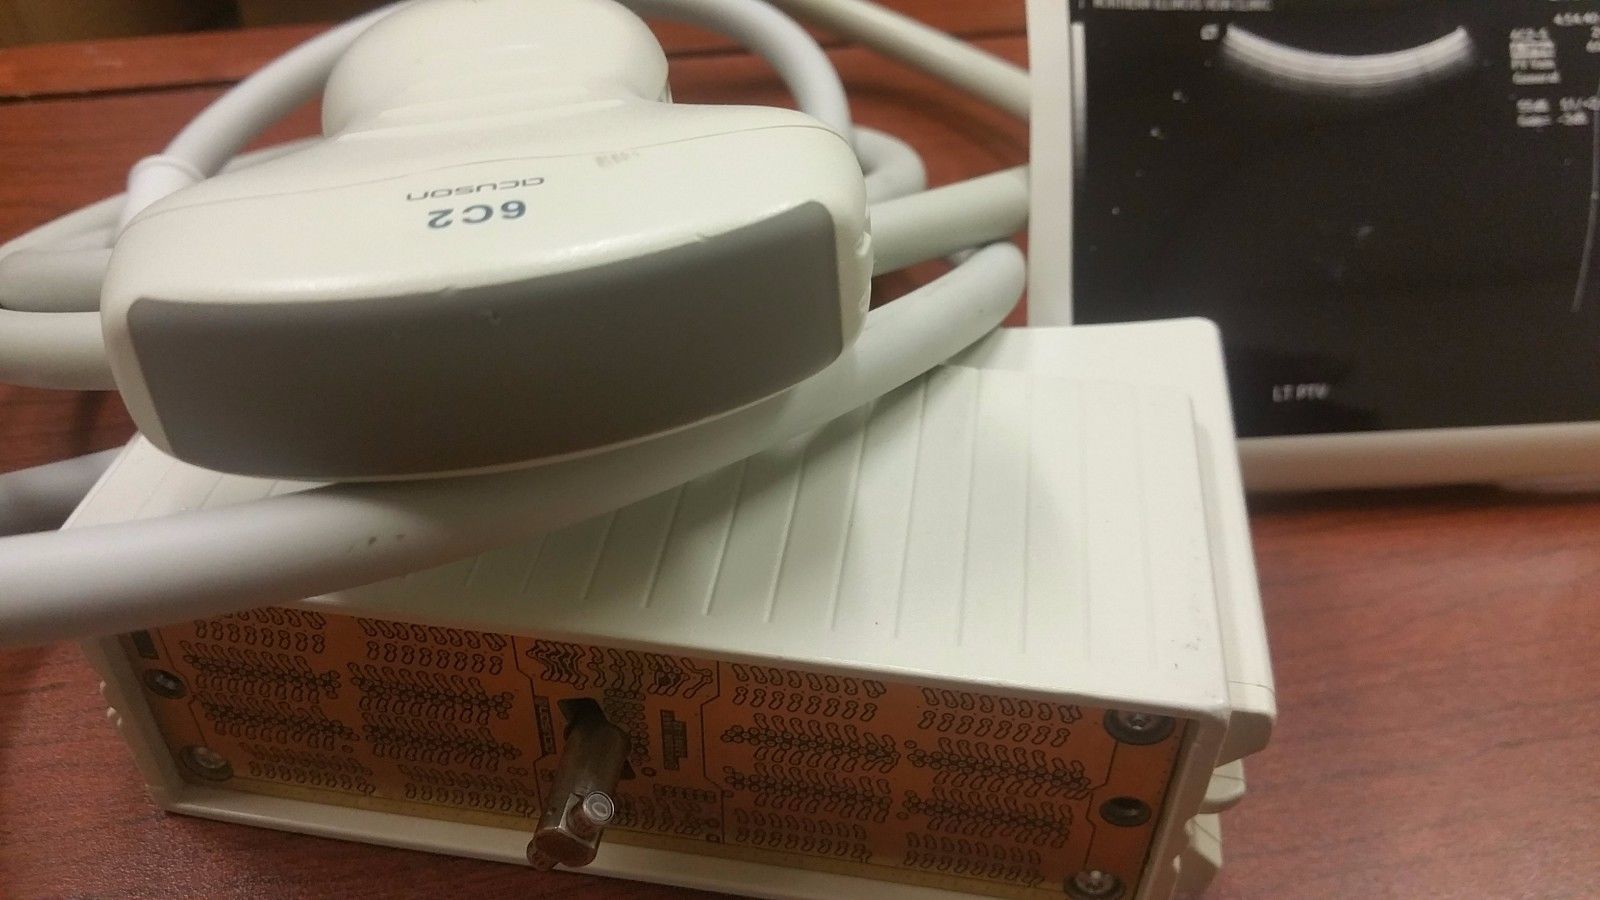

Acuson 6C2 Ultrasound Probe Transducer

The Acuson 4C1 Ultrasound Transducer Probe is a high-performance convex array probe designed for a wide range of clinical applications, including abdominal, obstetric, and gynecological imaging. Engineered for superior image clarity and deep tissue penetration, this transducer ensures accurate diagnostics with high-resolution imaging. Compatible with select Acuson ultrasound systems, the 4C1 probe offers excellent reliability and durability for continuous medical use. Its ergonomic design provides ease of handling, making it an essential tool for healthcare professionals seeking precision and efficiency in patient diagnostics. Whether replacing an existing transducer or upgrading your ultrasound equipment, this probe guarantees seamless integration and optimal performance. Each unit is tested and verified for quality assurance, ensuring consistent results in demanding medical environments. Available for fast shipping and competitive pricing, the Acuson 4C1 Ultrasound Transducer Probe is a trusted choice for professionals looking for accuracy and reliability in diagnostic imaging. Contact us today for pricing and availability.

Condition: Used